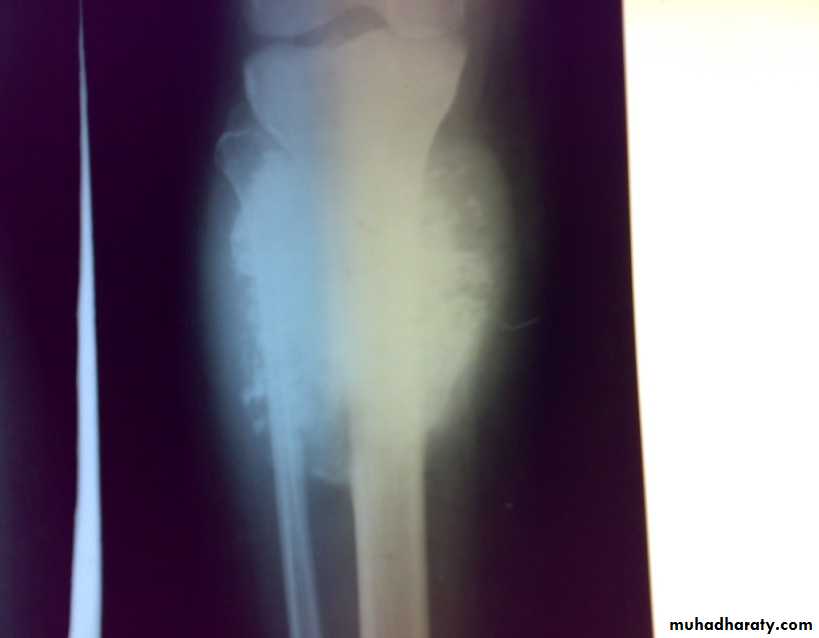

Osteosarcoma

primary malignant tumor arise from bone forming cells and produce malignant osteoid tissue. In addition to malignant osteoid tissue fibroblast or cartilage tissue may be predominate. It destroys the bone and form malignant osteoid and spread to surrounding tissue and metastasized to far organs.

Age : 10-20 years commonly but it may occur in old following irradiation and Paget’s disease.

Site: metaphysis of long bone specially around knee and proximal humerus is common sites.

: X-ray are very variable but it show combination of bone destruction and bone formation.

The metaphysis show osteolytic and osteoblastic areas, the cortex is usually perforated and soft tissue shadow may be seen.

There is new bone formation in form of Codman's triangle at periphery of when cortex penetration cause periostium elevation and vertical streaks of calcification in the adjacent soft tissues called sunray appearance.